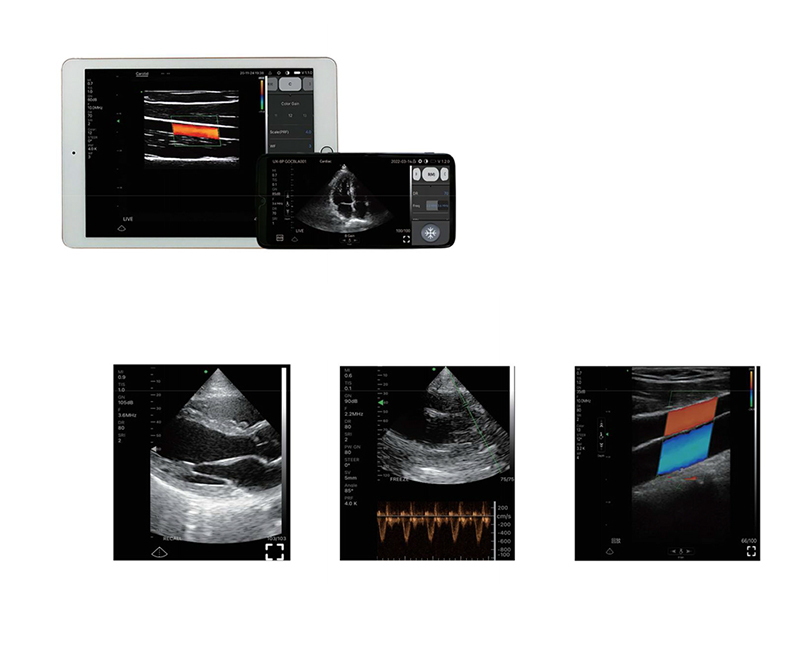

Wireless ultrasound probe" is a miniultrasound scanner that without screen.We made the main unit condensed into a small circuit board builded-in theprobe, and showing image in smartphone/tablet through Wifi transferring.-Image transferring through internalwifi from probe, no need external Wifi signal.

Clinical positioning >>>>>

Anesthesia, pain, care, ICU, emergency, ambulance,urology, hepatobiliary, endocardial, breast, physicalexamination, rehabilitation, bone injury, gynecology,obstetrics, reproductive, neonatal and otherdepartments, grassroots medical/family doctors, familyplanning stations, nursing homes, examination centers,nursing homes, postpartum care centers, plasticsurgery and beauty institutions, sports team medicalteams, military battlefield rescue medical teams,disaster rescue medical teams, etc.

Product Gallery